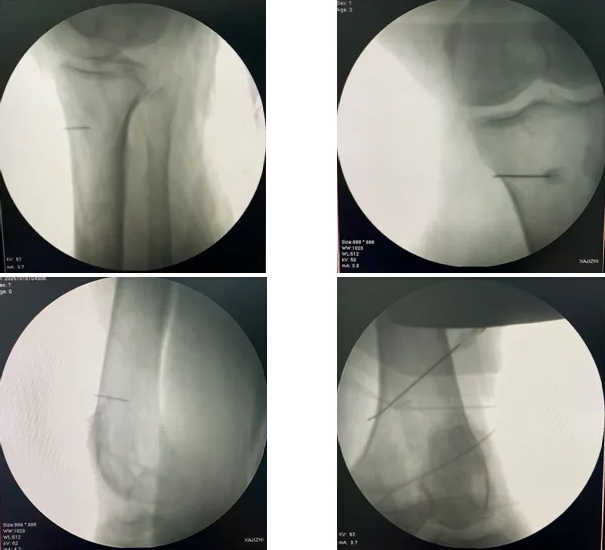

借助C臂透视设备,精准地将射频针定位到膝关节射频治疗部位,操作无需切口,仅需一枚细针,不对周围组织造成损伤,整个操作无痛苦,患者几乎无不适或疼痛感觉。

操作过程中,徐明杰主任和郝壮宇医师在局麻下行穿刺后,将射频电极导入。予以脉冲射频治疗,整个过程仅需要几分钟。操作后患者即刻感觉疼痛明显缓解。术后第二天患者下床活动自如,疼痛感消失,上下楼梯、蹲起等动作都能更轻松完成,生活质量大幅提升。